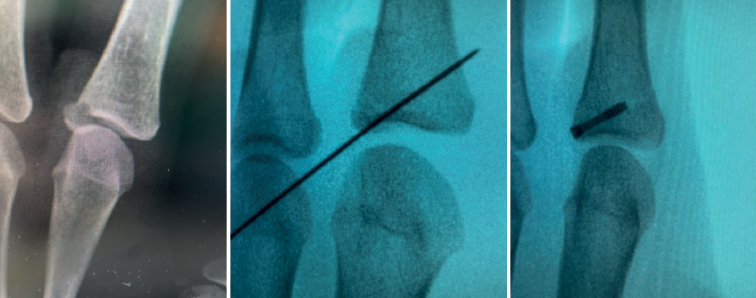

In terms of treatment, different authors advocate debridement of the insertional area of the ligament, reduction and correct positioning of the bone fragment, and its percutaneous fixation with Kirschner wires(1). Other authors advocate arthroscopy to locate and prepare the ligament and, by means of a minimal incision, re-anchor it(9).

Arthroscopically assisted reduction and percutaneous fixation of the avulsed fragment has several advantages over the open technique(5), including minimal aggression to the joint capsule, which usually serves to shorten the rehabilitation period. Furthermore, although not the subject of our study, the aesthetic result is more pleasing.

- Fractures with avulsion of the insertion of the collateral ligament (Figures 2 and 3).

Once the fragments have been reduced, 0.8 or 1.0 Kirschner wires are used to maintain reduction (Figure 7). Sometimes we can only maintain reduction by applying a stop, to prevent the osteochondral fragment from collapsing. Depending on the fracture pattern and the surgeon's preference, we can use conventional screws, cannulated screws, etc. (Figures 8 and 9).